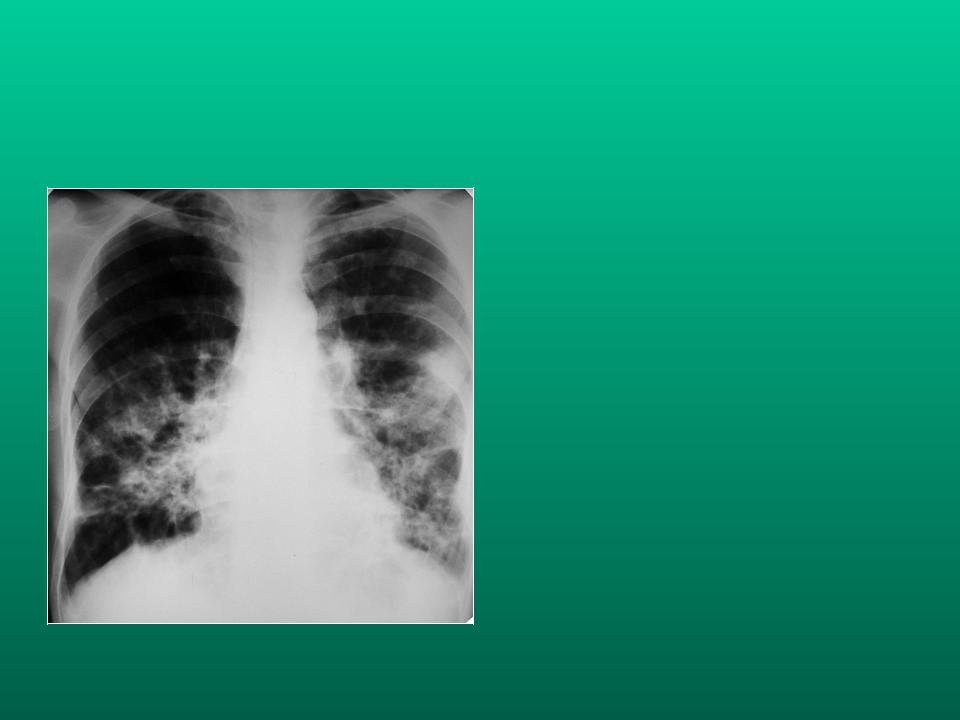

Синдром обогащения легочного рисунка рентген